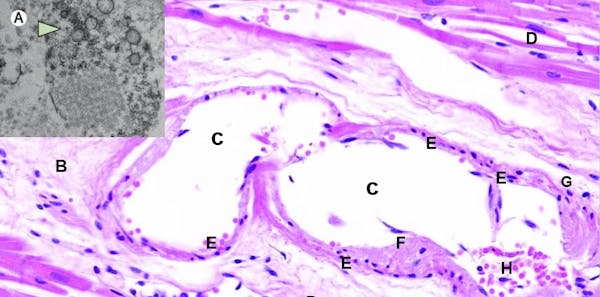

Los investigadores chinos ya habían publicado el 9 de marzo la relación entre el dímero-D y la gravedad de la COVID-19. En la Figura 2 puede comprobarse cómo, a medida que transcurren los días, en los pacientes que van a fallecer va aumentando el riesgo de formación de trombos, cuyo indicador es el incremento en los niveles de dímero-D.

Varga et al. 2020

Tanto las células epiteliales de los alvéolos pulmonares (neumocitos) como los endotelios vasculares disponen de receptores ACE2 en abundancia. Este receptor es la cerradura que encaja a la perfección con la proteína espiculada del virus, de forma que estas células abren sus puertas de par en par a la entrada del coronavirus, lo que provoca una endotelitis, es decir, una inflamación del endotelio vascular (Figura 3).